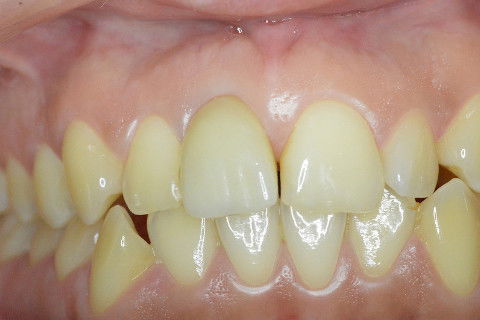

Sorriso da paciente no dia da colocação da coroa

Contornos gengivais compatíveis com os dentes adjacentes

Vista mais aproximada dos contornos gengivais

Aspecto do sorriso após colocação de resina composta na mesial do element 21 afim de deixar os centrais com a mesma largura